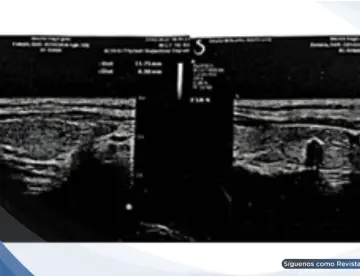

<p>La tomografía torácica y la <strong><a href='https://medicinaysaludpublica.com/tags/broncoscopia/54407' target='_blank'>broncoscopia</a></strong> confirmaron una hemorragia pulmonar secundaria a trombosis de la vena cava superior, evidenciando un diagnóstico poco frecuente que puede imitar una emergencia digestiva.</p>

<h1><strong>Evaluación inicial: Sin evidencia de <strong>sangrado</strong> digestivo activo</font></strong></h1>

<p>La endoscopia digestiva alta mostró várices esofágicas pequeñas y gastropatía erosiva, pero sin <strong>sangrado</strong> activo que justificara la gravedad del cuadro. Este hallazgo obligó a ampliar el enfoque diagnóstico, considerando causas no gastrointestinales.</p>

<p>En este contexto, la tomografía computarizada de tórax reveló un hallazgo clave: trombosis de la vena cava superior con abundante circulación colateral mediastínica. Además, se evidenciaron áreas de consolidación alveolar compatibles con hemorragia pulmonar y un derrame pleural derecho.</p>

<strong>Confirmación diagnóstica</font></strong></h2>

<p>La <strong>broncoscopia</strong> fue determinante al identificar <strong>sangrado</strong> activo en el árbol bronquial derecho con presencia de coágulos adheridos, confirmando que la fuente del <strong>sangrado</strong> era respiratoria y no digestiva.</p>